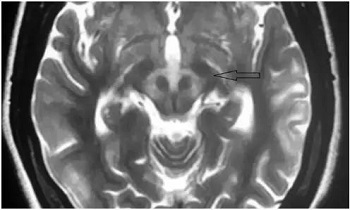

在查房的间隙,贾映海教授便在走廊里继续开讲起“走廊课堂”——“何谓熊猫征”来。贾映海教授说,“熊猫征”主要有“大熊猫脸征”和“小熊猫脸征”。其中,“大熊猫脸征”,红核在T2WI上呈现对称性的低信号,为大熊猫的眼,红核周围的内侧丘系、大脑脚上部、红核脊髓束及皮质脑干束神经纤维受累表现为T2高信号, 构成大熊猫脸上半部白色的轮廓;而双侧上丘、中脑导水管周围灰质神经核团正常的短T2信号及中脑导水管的长T2信号构成了大熊猫脸的下半部。

贾映海教授接着说,“小熊猫脸征”,中脑下部层面的双侧大脑脚、 上丘、 导水管、 导水管周围灰质核团、中央上核等构成了小熊猫脸的大体结构, 而双侧受累而呈长T2 信号的红核周围纤维束与短T2的中央被盖束勾勒出小熊猫的双眼。

贾映海教授说,熊猫征绝大多数为Wilson病(肝豆状核变性)的典型特征,也有个案报道见于Leigh病(亚急性坏死性脑脊髓病)。